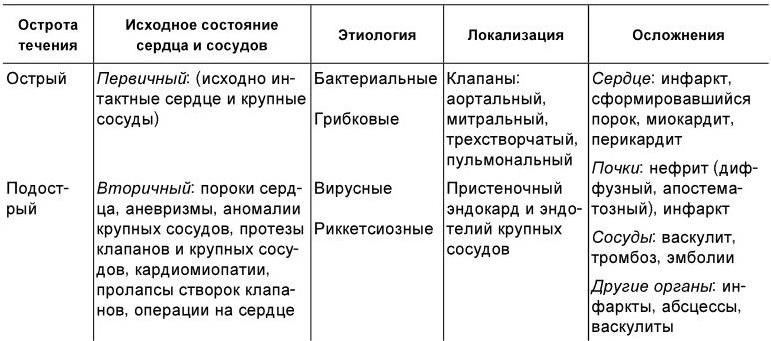

Классификация инфекционных эндокардитов отражает исходное (до начала заболевания) состояние сердечно-сосудистой системы, этиологию, локализацию патологического процесса, остроту течения, наличие осложнений (табл. 1.12).

Таблица 1.12

Классификация инфекционного эндокардита

С учетом исходного состояния сердечно-сосудистой системы различают первичный и вторичный инфекционный эндокардит. Первичный эндокардит возникает при исходно интактном сердце, вторичный – у больных с предсуществовавшими изменениями сердца и крупных сосудов (пороки, кардиомиопатии, аневризмы и др.).

Острый инфекционный эндокардит является одним из проявлений острого сепсиса. Поэтому под термином инфекционный эндокардит обычно подразумевают заболевание подострого течения (в прошлом использовался термин подострый инфекционный эндокардит).